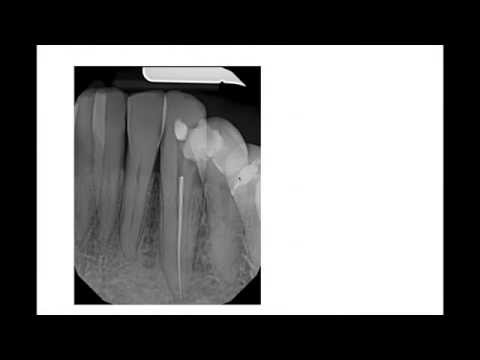

Removal of broken instrument

How to remove a broken file from the root canal (1)

Removal Of Separated Instrument in Endodontics